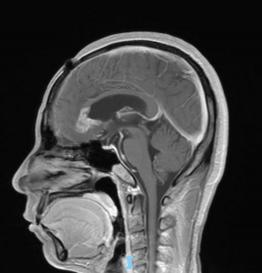

44歲的郭先生(化姓)為膠質(zhì)瘤復(fù)發(fā)患者,復(fù)查發(fā)現(xiàn)顱內(nèi)占位進(jìn)行性進(jìn)展1周,MRI檢查提示瘤體已累積到胼胝體,且瘤體位置較深,手術(shù)難度極高。面對這一挑戰(zhàn),王虎教授團(tuán)隊(duì)決定采用多種先進(jìn)技術(shù)輔助手術(shù),其中最為引人注目的就是首次引入的細(xì)胞級顯微鏡EndoSCell?。該設(shè)備是目前全球唯一實(shí)時(shí)在體細(xì)胞級顯影的儀器,可以輔助醫(yī)生從細(xì)胞層面區(qū)分腫瘤組織與正常組織,從而做到細(xì)胞級精準(zhǔn)切除。

患者術(shù)前核磁影像